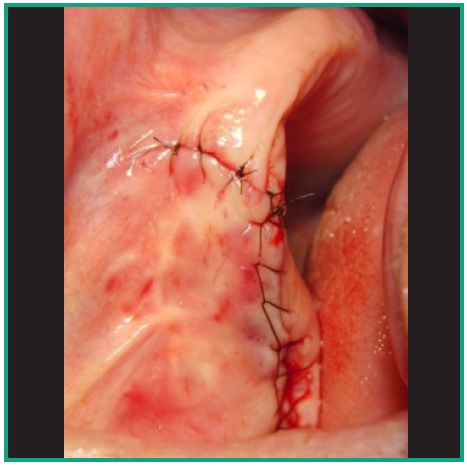

Se procede a hacer ostectomía con instrumental rotatorio y abundante irrigación con suero fisiológico, con la finalidad de agrandar la fenestración para facilitar la visibilidad. Con curetas de elevación sinusal se realiza la eliminación total de la lesión mediante la técnica de enucleación y curetaje, procediendo luego a hacer la exéresis del tabique óseo que divide dicha patología (Figs. 7, 8, 9). Por último se realizó un cierre mediante sutura continua con nylon 5 cero (Fig. 10).

En el post operatorio se indica Amoxicilina 500 mg. cada 8 horas durante 10 días, Ibuprofeno como analgésico y antiinflamatorio a razón de un comprimido de 400 mg. cada 6 horas durante un período de 48 a 72 horas. Como no se realizó contrabertura en el meato inferior se le prescribió gotas nasales con vasoconstrictor para mantener permeable el ostium, facilitando de esa manera el drenaje hasta darle el alta al paciente. A los diez días se retiró la sutura, controlando la evolución cada semana por un período de 2 meses (Fig. 11).